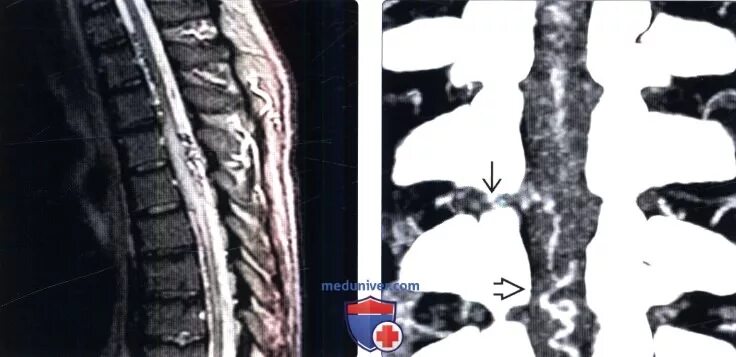

Деформация дурального мешка поясничного